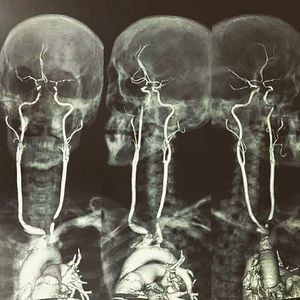

Here is an contrasted MRI showing the origin & length of the carotid arteries. The carotid arteries are major blood vessels in the neck that supply blood to the brain, neck, and face. There are two carotid arteries, one on the right and one on the left. In the neck, each carotid artery branches into two divisions, internal & external carotid arteries. - Mention your friends to see this Follow us @medshots for more